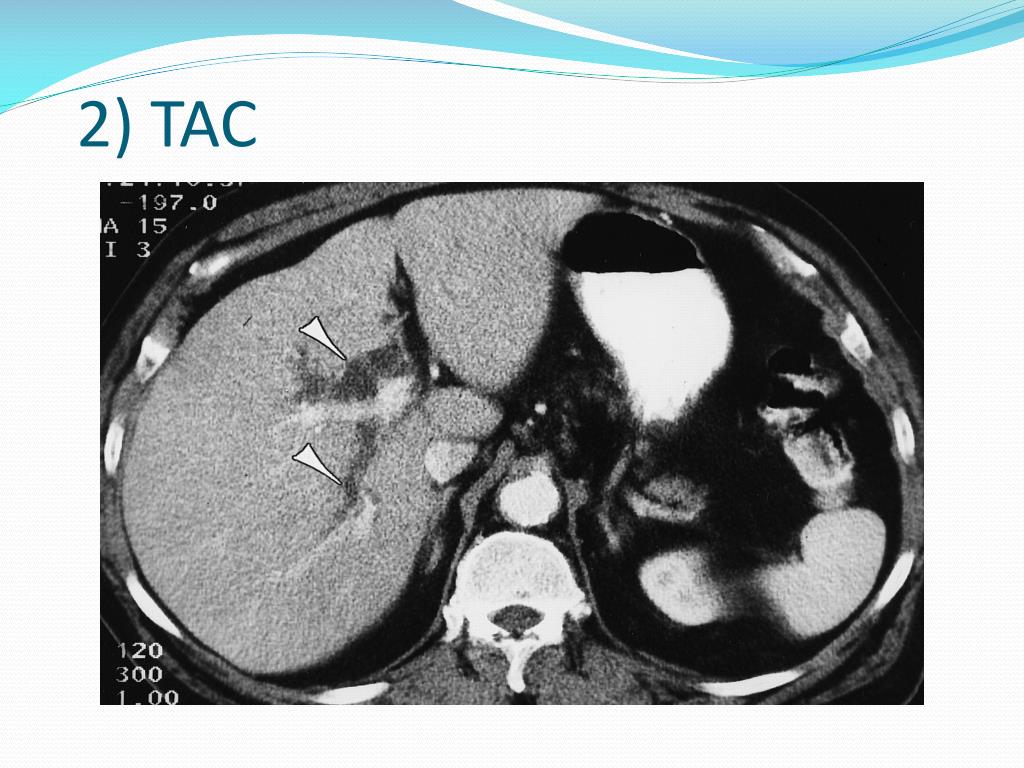

16. 2) TAC

14. Diagnostica per immagini: • ECOGRAFIA: indagine iniziale d’elezione nei sospetti clinici e laboratoristici. Dilatazione del coledoco e anche delle vie biliari intraepatiche a monte dell’ostruzione (diametro > 7-8mm) NB:pazienti anziani o colecistectomizzati (diametro > 10mm); carattere intermittente; • TAC: utile negli obesi o nei pazienti con sovradistensione gassosa (più utile nei tumori) • COLANGIO-RM: diagnosi di conferma • COLESCINTIGRAFIA (acido iminodiacetico marcato con 99mTc: HIDA)